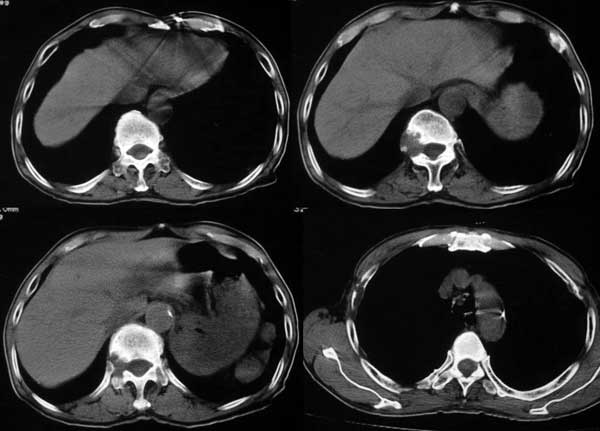

附肾脏平扫及增强片

肺及胸膜下多发结节影,胸椎及附件、肋骨破坏支持转移癌。气管内结节影支持痰核。肾脏ct应该是术前的吧?左肾内亦见一低密度灶,另外胰腺好像也不规则。不知术后结果如何?

左侧肾癌,腹膜后淋巴转移,肺及胸椎转移,右肾转移可能,气管内痰栓可能[壁可见]

左侧肾癌伴腹膜后淋巴结、胸椎、双肺内转移。

肾癌.双肺,胸椎及肋骨转移.